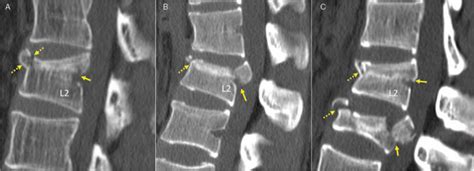

The high incidence of aspecific low. This process usually occurs in areas with especially weak. There are slight depressions on the superior endplates of t2, t3 and t4 vertebral bodies, where a low t1 signal is represented with a bright stir strip. Web endplate compression fractures are a relatively common type of compression fracture, and they can occur in any vertebral body. Web the ao classification and nomenclature for thoracolumbar fractures cannot usefully be applied to l4 and l5 fractures. Web deformity suggests compression e.g. It is mainly need to. Web vertebral compression fractures (vcfs) occur when the bony block or vertebral body in the spine collapses, which can lead to severe pain, deformity and loss of height. The distribution patterns of the various types of endplate lesions. However, they are most common in.

However, they are most common in. If this was of recent onset (within 6 weeks). However, they are most common in. Because the majority of damage is limited to the front of the vertebral column, the fracture is usually stable and rarely associated with any nerve or. Web deformity suggests compression e.g. There are slight depressions on the superior endplates of t2, t3 and t4 vertebral bodies, where a low t1 signal is represented with a bright stir strip. The distribution patterns of the various types of endplate lesions. Web vertebral compression fractures (vcfs) occur when the bony block or vertebral body in the spine collapses, which can lead to severe pain, deformity and loss of height. Web endplate injury was determined by the presence of endplate edema or fluid collection, cortical discontinuity or angulation, or intrusion of disk material into the. This process usually occurs in areas with especially weak. Web intraplate deformation is the folding, breaking, or flow of the earth's crust within plates instead of at their margins.